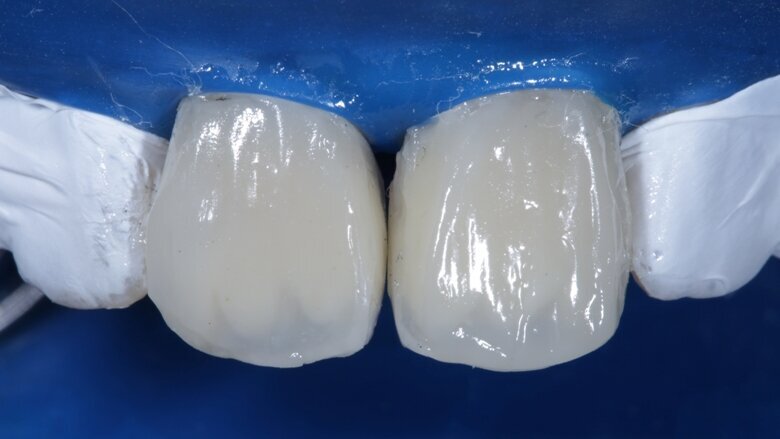

Desaturation was achieved by layering a deeper darker dentin [ A3 Dentin - Fig 12 ] inside and a lighter dentin [ A2 Dentin - Fig 13 ] shade over it in the shape of three mamelons. Incisal Halo was achieved by layering an Achromatic Enamel [clear translucent] shade around the mamelons [ Fig 14 ] and the A2 dentin shade on the incisal edge [ Fig 11 ]. Final layer of A2 Enamel shade was used covering the restoration in 0.5mm thickness so as to avoid too much translucency [ Fig 15 ]. Finishing and polishing were done using the 3M Soflex discs and spirals [ Fig 17 ] as recommended by the manufacturer.

Fig 15 Final enamel layer